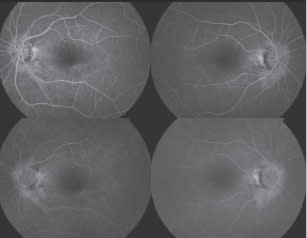

| Case 2: Retinal Detachment vs Schisis |

A 45-year-old woman is evaluated for sudden vision loss in the right eye. Clinical examination revealed an elevation of the right inferotemporal retina, suggesting retinal detachment. Cirrus HD-OCT revealed that it was not a retinal detachment, but was instead a retinal schisis, which can be safely observed in most patients and does not require immediate treatment.